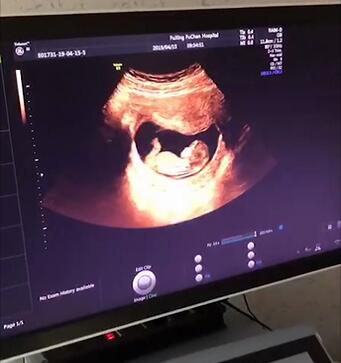

孕中期四维彩超

做四维彩超的最佳时间为怀孕22-26周,因为这个时段胎儿的肢体及各主要脏器已经全部发育,而且羊水较适合做胎儿畸形筛查。

做四维彩超,可清晰展现胎儿各部位脏器,了解胎儿生长发育情况,观察头,肢体及各脏器大体结构是否有畸形。另外还要定期检查胎心、血压等等。